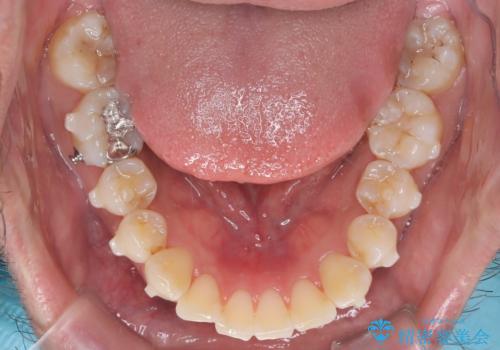

【インビザライン】前歯の凸凹を解消。

- 前歯の凸凹を主訴に来院されました。

もともと、顎が左にシフトしていたので正中が合わないことを説明した後、矯正を開始しています。

短期間で前歯のがたがたがきれいになり、満足していただけました。